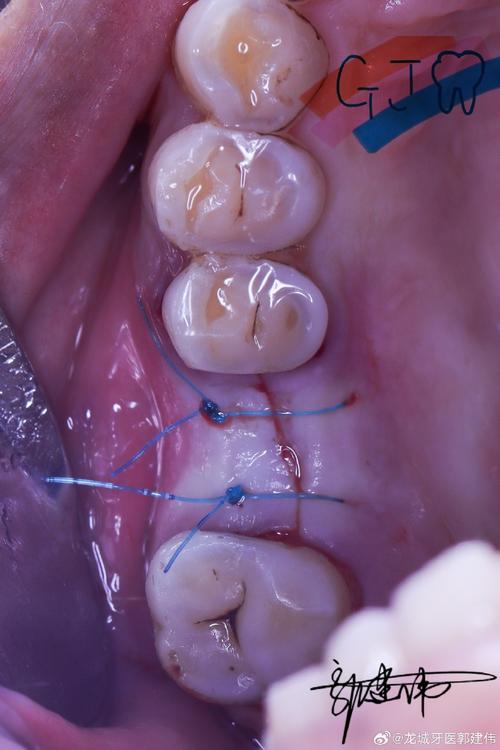

(图片来源网络,侵删)- 了解机构提供哪些主流品牌的种植体?不同品牌在稳定性、成功率、价格、适用人群上差异较大。